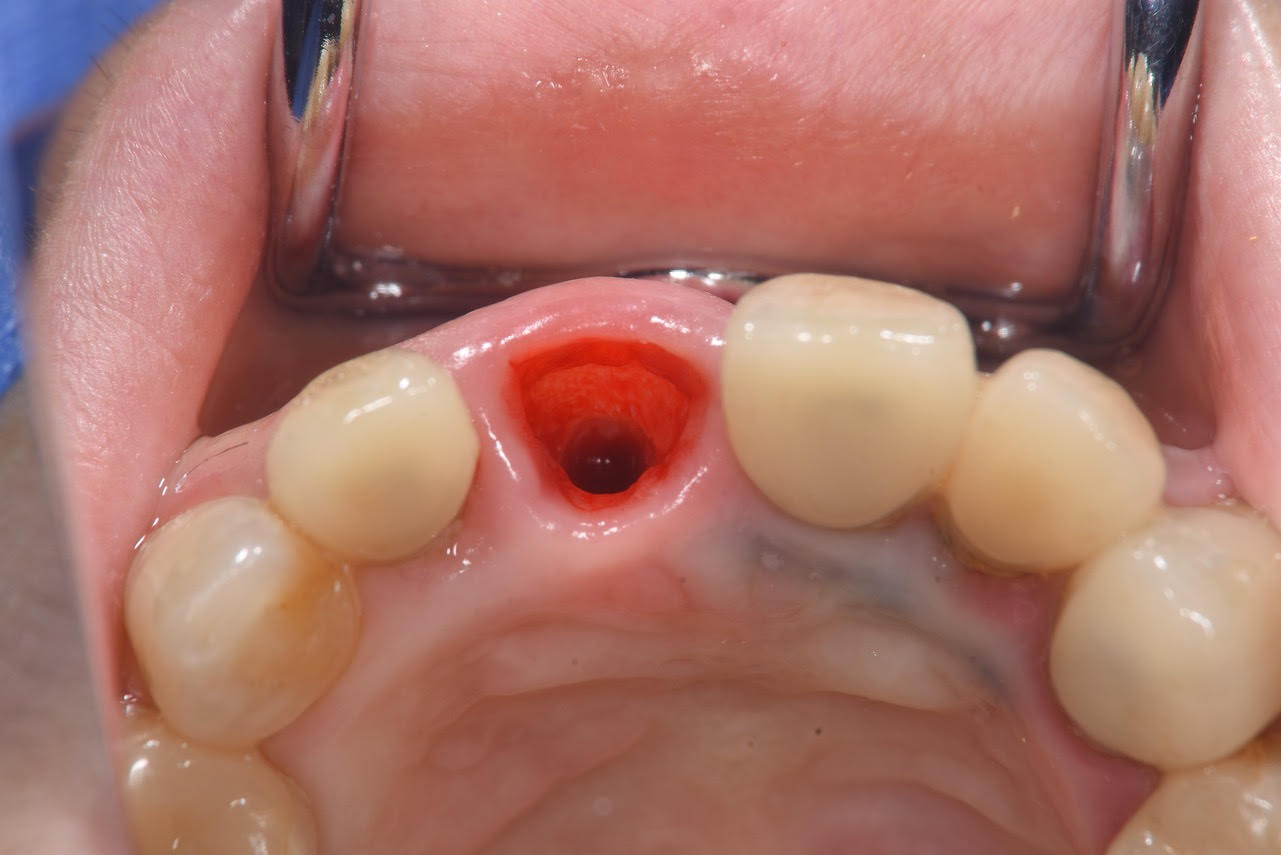

4. 治療時:切らない・縫わない・腫れない手術

実際の手術は、事前にシミュレーションした位置へ正確にインプラントを埋入します。

当院のこの術式の強みは、「フラップレス手術(無切開手術)」であることです。

メスで歯ぐきを大きく切ったり、縫合したりする必要がありません。そのため、術後の腫れはほとんどなく、患者さんも「もう終わったのですか?」と驚かれるほどスムーズに終了しました。

また、今回は「同時仮歯作製」を行いました。

手術当日に、見た目を回復する仮歯をお入れしています。これにより、「歯がない期間」をゼロにすることができ、手術直後から人目を気にせず生活していただくことが可能になりました。